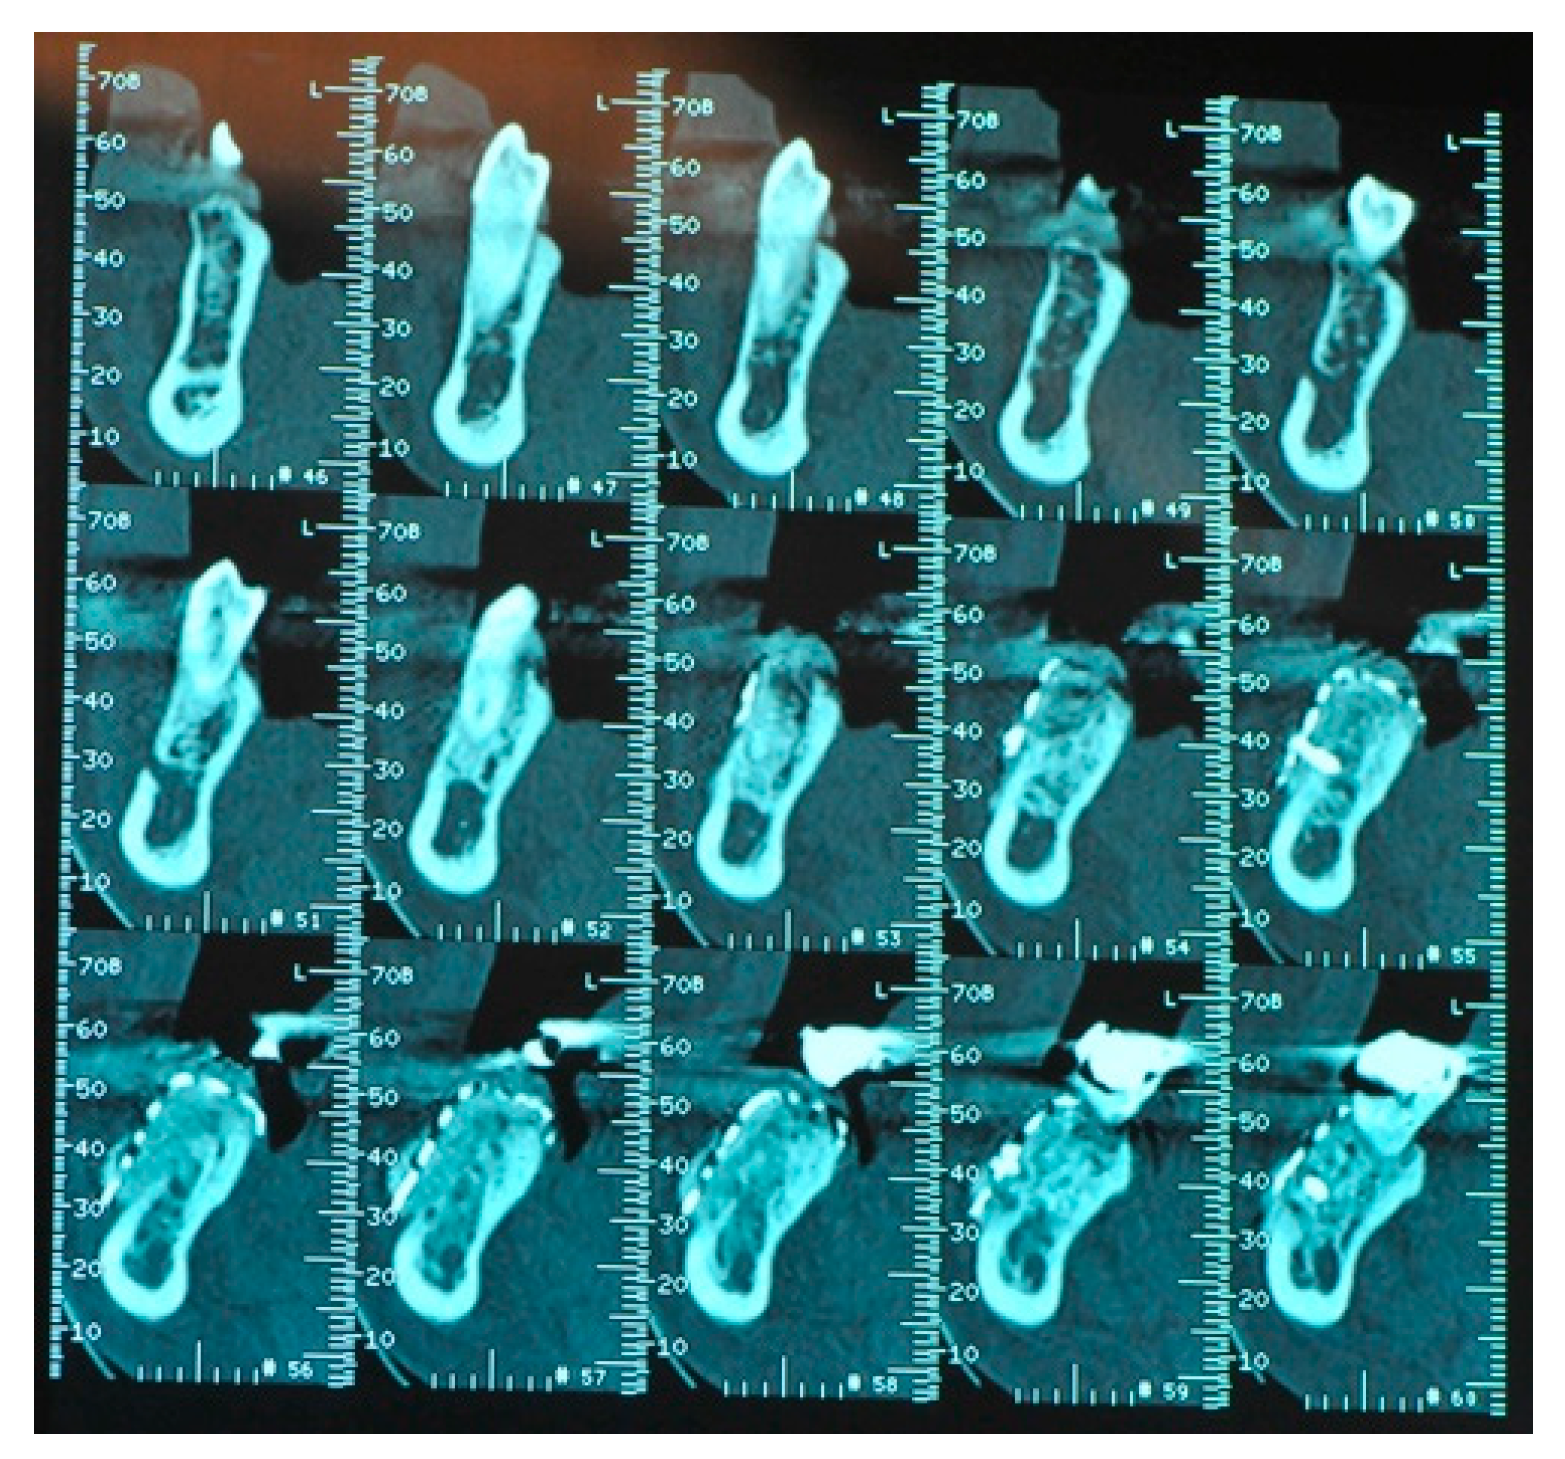

- The presence, clinically and radiographically (intraoral radiographs, panoramic, CT scans) assessed, of horizontal, vertical or mixed bone defects of the maxillary bones in particular the presence of residual bone <8 mm in height and <5 mm in width.

- Flap design: Soft tissue management should be as accurate as possible. The design of the flap should ensure a tension-free primary closure of the wound even after voluminous grafting of the defect. One option (preferred especially in wide vertical defects) is the execution of the so-called “poncho” flap. This technique includes a high vestibular incision of the mucosa, muscle and periosteum in order to undermine the preparation of the flap and to achieve its mobilization, followed by a deep incision in the buccal area with two additional vertical incisions that are performed at an appropriate distance from the occlusal area and the site of augmentation. After the incision, the preparation of a muco-periosteal flap and the remotion of scar tissue, a full thickness flap is raised until the bone defect is uncovered [17,18,19,20]. Finally, the positioning of the customized titanium mesh is passively tested to evaluate its fit intra-operatively (Figure 2, Figure 3, Figure 4 and Figure 5).